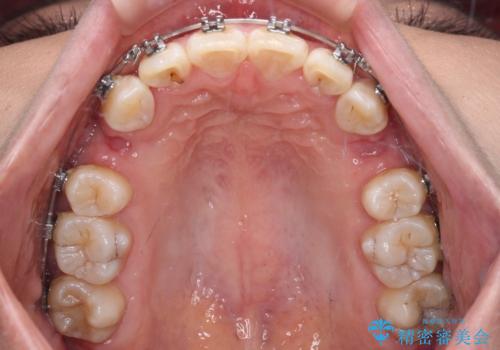

- メタルブラケット

骨格的に上顎歯列が前方位にあり、口元の突出感が顕著な状態で、上下左右の第一小臼歯4本を抜歯して、ワイヤー装置での抜歯矯正を行うこととしました。

奥歯の咬み合わせ改善のために、アンカースクリューの使用と上顎左右第一小臼歯の抜歯のタイミングをコントロールして、理想的な咬み合わせに仕上げていくこととしました。